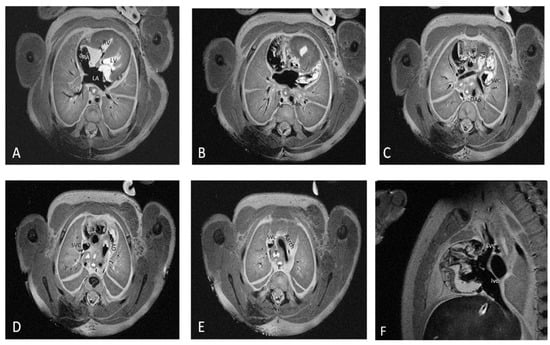

For each structure, the imagists examined normal or abnormal morphological aspects and mentioned the observed abnormal morphological aspects. Figure 1 depicts the fourteen cardiac items evaluated.

Figure 1.

The fourteen cardiac items evaluated using 7T pm-MRI (T2, WI) depicted in a control case. Seventeen weeks of gestation-age fetus resulted from therapeutic interruption of pregnancy due to severe hydrocephaly with normal cardiac imaging evaluation and was confirmed by conventional stereomicroscopic dissection. Transvers section through the mediastinum depicting: (A) four chamber view with interatrial and interventricular septum, atrioventricular valves, left atrium (LA), right atrium (RA), left ventricle (LV), right ventricle (RV) and two pulmonary arteries, and esophagus (E); (B) aortic valve (Av), esophagus (E), aorta (Ao), and azygos vein (Az); (C) pulmonary artery (PA), ascending aorta (Aa), descending aorta (Dao), and superior vena cava (SVC); (D) arterial duct (AD); (E) aortic arch (Aarch) and trachea (T); and (F) sagittal section through the mediastinum depicting inferior vena cava (IVC) and SVC.

The data set included 168 structures (12 cases × 14 structures for each case). All items included were properly visualized using pm-MRI.